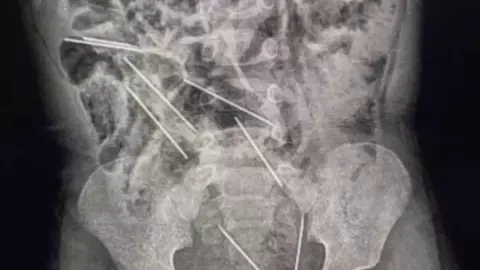

Por medio de una radiografía realizada al bebé, se pudo constatar que las agujas se encontraban en su sistema digestivo, por lo que tuvo que ser sometido a una cirugía de emergencia.

A pesar de lo crítico del asunto, personal médico realizó una intervención quirúrgica de aproximadamente dos horas para poder remover los alfileres de su cuerpo.

Cabe señalar que las agujas que fueron extirpadas de su cuerpo, se encontraban muy cerca de sus órganos vitales, por lo que se considera un milagro que el pequeño haya podido salvarse.